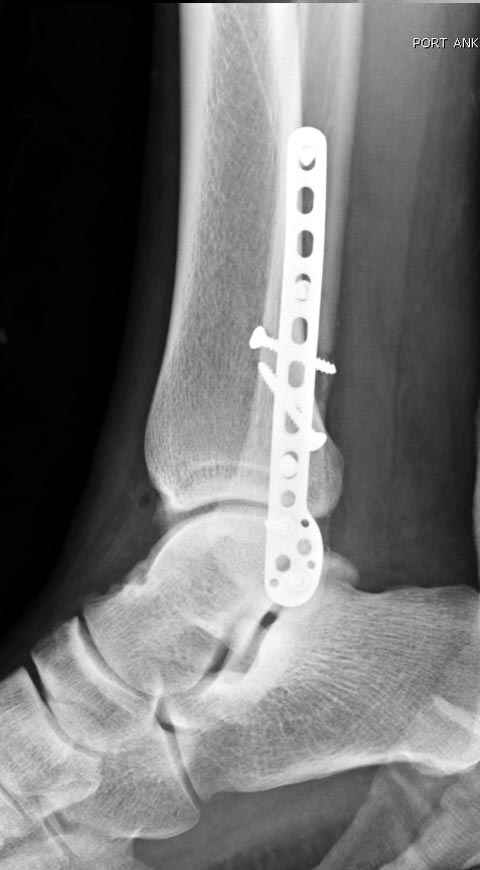

Уважаемые коллеги! Как и обещал, представляю плоды своей работы. Хвалиться особо нечем. Пошли задним

доступом сначала к м/берцовой кости, благодаря смещению линию перелома удалось сразу дифференцировать и по ней узким долотом (без молотка) мобилизовали отломки. Затем выделили задний край, там было проще пройти по линии перелома. Далее пластина по задней поверхности в дистальный отломок, винт проксимальнее пластины и дистрактором с трудом растянули отломки, ощущение было идеальной репозиции м/берцовой кости( доступен осмотр по задней и наружной поверхности), далее винты стандартно. Кстати, положение больной на боку: очень неудобно, но по-другому потом не повернуть на спину, чтобы сделать снимки в стандартных проекциях (ЭОПа нет). Затем дистрактор (два полукольца, спицы), репозиция заднего края, спонгиозный винт с шайбой, слишком проксимально, поэтому + еще один. Доступ к дельтовидной связке: рубец в передней порции, частично иссечен, шов. В общем, длительность операции 3,5 часа, а сказать, что все задуманное получилось, не могу.

Отличная, грамотная работа, поздравляю, я бы держал в гипсовой повязке до трех недель, затем разработку сустава без нагрузки, нагрузку при такой фиксации,

думаю, можно начать в 6 недель.

Все таки нужно было стянуть ДМС. Судя по снимкам остался подвывих.

Да все прилично получилось, и случай ведь запоздалый, так что все труднее было, чем обычно. Так что присоединяюсь к поздравлениям!